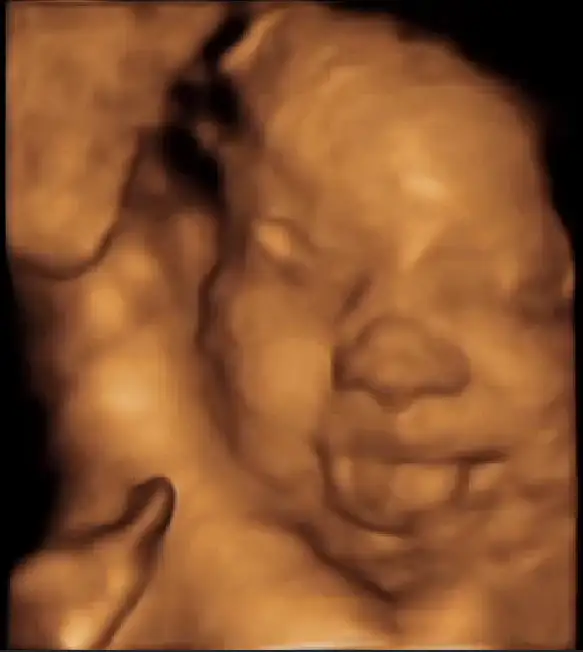

Benim de sağ kasığım çok ağrıyor adım atamıyorum dedim . Bebek çapraz duruyormus başı sağ kasığımın üstüne yerleşmiş olduğu için kemik yapı baskı yapıyormus . Ebe aarkadaşlarından egzersiz için destek al başını ortalamamız lazım , yoksa normal doğum sıkıntıya girer dedi . Aksak yürüyüş falan yapıcaz bakalım :/